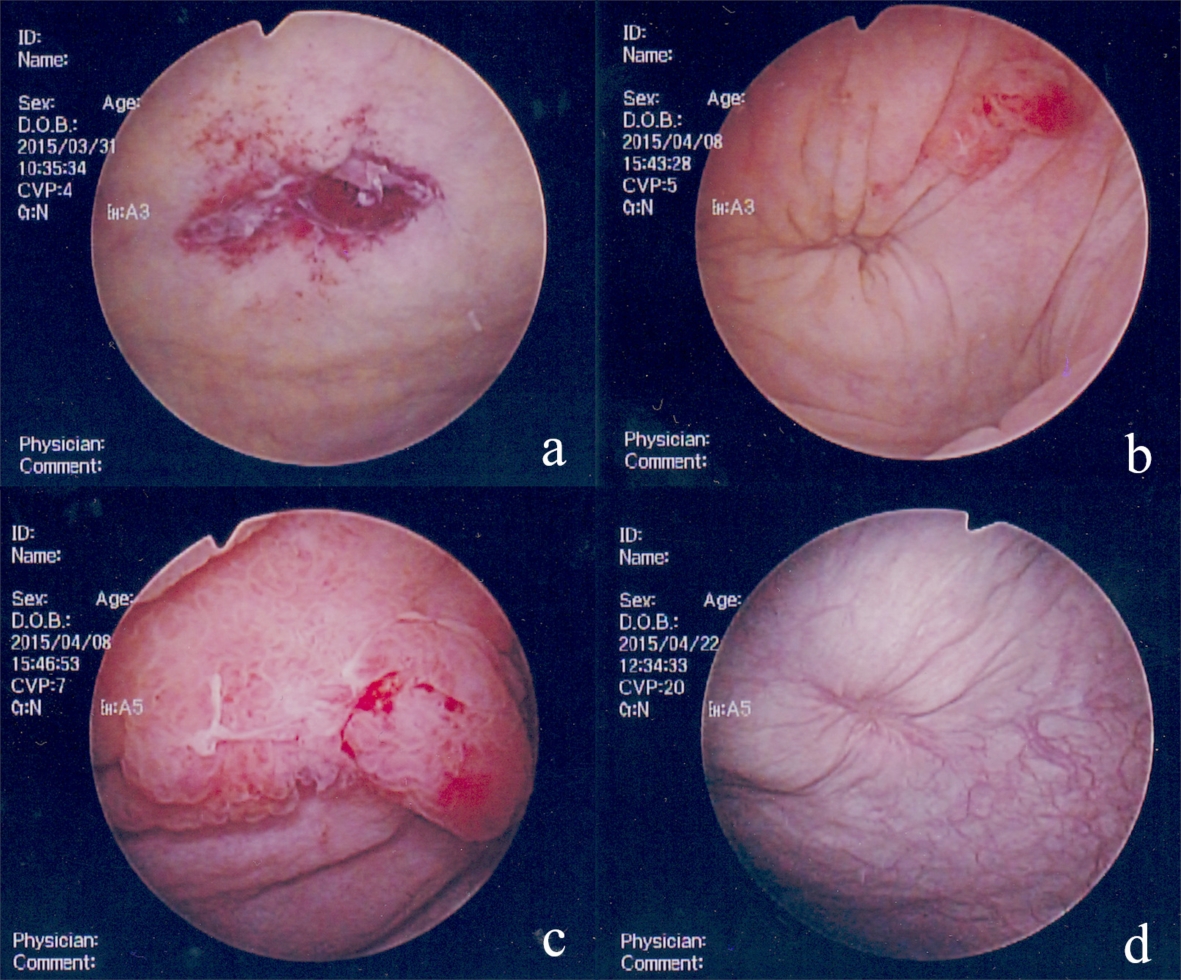

Three days after admission, cystoscopy revealed a small perforation on the right side of the bladder dome (Fig. 2a). The patient was diagnosed with intraperitoneal bladder rupture, and a renal pelvic balloon catheter was placed after cystoscopy. Four days after admission, a second non-contrast CT scan detected loss of fluid in the abdominal cavity (Fig. 1c). Five days after admission, a cystogram showed extravasation of contrast agent from the bladder dome (Fig. 3). Conservative management was continued because urine could be constantly drained and her general condition and laboratory data had improved.

![]() Click for large image | Figure 2. Findings from cystoscopy. (a) A small tear with blood clots at the bladder dome at 3 days after admission. (b) An obstructed tear and a papillary tumor on the left side of the tear at 11 days after admission. (c) An enlarged papillary tumor at 11 days after admission. (d) Healed bladder rupture at 11 days after discharge. |

Eleven days after admission, cystoscopy showed no perforation at the bladder dome (Fig. 2b), but a papillary tumor was found on the left side of the perforation scar (Fig. 2c). We performed a cold punch biopsy because cytology findings indicated a class IIIb tumor. The pathological findings showed papillary cystitis. Fourteen days after admission, a third CT cystogram showed no extravasation of contrast agent (Fig. 1d). The patient was discharged in good condition because she could urinate after urethral catheter removal. Eleven days after discharge, cystoscopy revealed no perforation or papillary tumor (Fig. 2d), indicating that the bladder rupture had healed under conservative non-operative management.